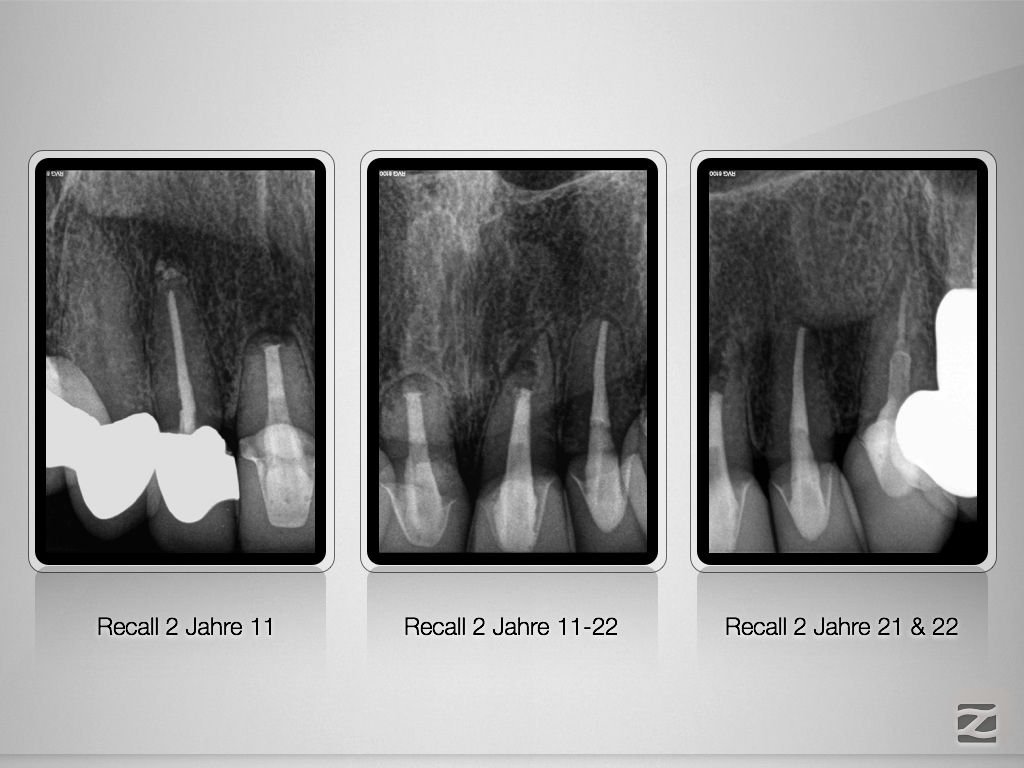

Saving Hopeless Teeth – Zustand nach WSR